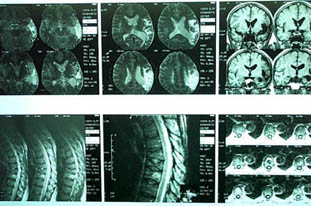

Differentiation of Malignant Vertebral Collapse from Osteoporotic and

Other Benign Causes Using Magnetic Resonance Imaging

D Y L Tan,*MBBS, FRCR (UK) , I Y Y Tsou,*MBBS, FRCR (UK) , T S G

Chee,**FAMS, MBBS, FRCR (UK)

Abstract

Introduction: Elderly patients presenting with backache and vertebral

collapse are a diagnostic challenge. Plain X-rays, computed

tomography and radionuclide bone scans have not always reliably

distinguished between benign and malignant causes. Magnetic resonance

imaging (MRI) may be able to do so. Materials and Methods: Patients

who underwent MRI evaluation for vertebral collapse were

retrospectively studied. Over a 21-month period from January 1995 to

September 1996, 47 patients with 58 vertebral collapses were studied.

Benign and malignant aetiologies were established by serial imaging,

clinical outcome and histology. Imaging was performed with T1 and

T2-weighted sequences, with contrast enhancement in some patients.

Collapsed vertebrae were examined for appearance of marrow on T1

and T2-weighted sequences and after contrast administration, signal

intensity of adjacent discs, degree of marrow involvement, involvement

of posterior elements, presence or absence of paraspinal mass and

end-plate integrity. Agreement between the final and radiological

diagnosis was evaluated. Results: There were 36 benign vertebral

collapses (20 osteoporotic, 7 post-traumatic, 9 infective) and 22

malignant ones (20 metastatic carcinoma, 2 multiple myeloma). Features

which pointed t o malignant cause were hypointense marrow on

T1-weighted images, marrow enhancement after intravenous contrast,

greater than 50% marrow involvement and involvement of posterior

elements. Of the vertebral collapses due to infection, 78% showed

end-plate disruption. Conclusions: This study shows that MRI can be

used to accurately differentiate between benign and malignant causes

of vertebral collapse. Further differentiation between an

osteoporotic, traumatic or infective cause can be done with the help

of clinical history and evaluation of end-plate integrity.

Ann Acad Med Singapore 2002; 31:8-14